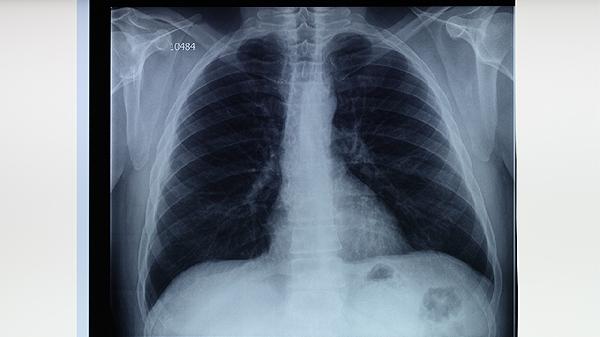

肺结核患者应注意保持居室通风,避免随地吐痰。饮食应保证足够热量和优质蛋白摄入,如鸡蛋、瘦肉、豆制品等。适当进行散步、太极拳等温和运动有助于增强体质。治疗期间应严格遵医嘱用药,不可自行停药,定期复查胸部影像学和肝肾功能。出现药物不良反应如皮疹、黄疸时应及时就医。密切接触者应进行结核菌素试验筛查,儿童接触者必要时可预防性服用异烟肼。